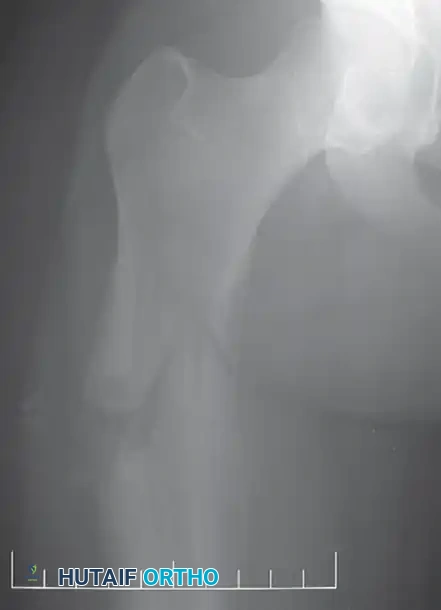

A: Anteroposterior radiograph of the right knee in a 50-year-old woman presenting with progressive pain. An expansile lesion is visible in the proximal fibula, containing classic "popcorn" calcifications highly suggestive of a cartilaginous tumor.

B: Coronal T1-weighted MRI confirms the lesion remains entirely contained within the fibular cortex, with no soft-tissue extension.